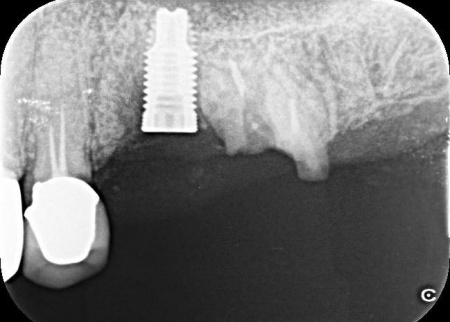

拝見したところ、左上奥歯(第2小臼歯)1本が折れ、歯根だけの状態になっていました。

レントゲン撮影をして詳しく検査した結果、治療して温存することは困難な状態だったため、残っている歯根を抜き、欠損部分を補う治療が必要だと判断しました。

患者様は、人工歯根であるインプラントによる治療を希望されていましたが、レントゲン撮影の結果では、インプラントを入れるために必要な骨の量が足りていません。

まず、左上奥歯を抜きます。

続いて、不足している骨を補強しつつ、インプラントを埋入した土台を安定させるための骨補填を行いました。

3ヶ月後、顎の骨の状態が良好であることを確認し、インプラントを埋入する手術を実施しました。